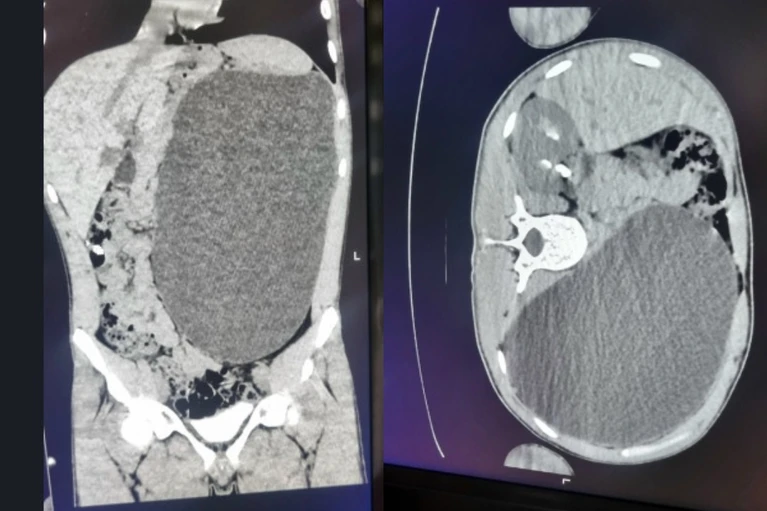

- Это была случайная находка. Ему перед трудоустройством сделали УЗИ, нашли объемное образование в брюшной полости. Мы стали обследовать, оказалось, что это гидронефроз левой почки с отсутствием основной ткани органа, выполняющей его функции, – рассказала детский хирург-уролог Ирина Живолуп.

- У нашего пациента почка достигла размеров пятилитровой бутылки! Она занимала почти весь объем живота и давила на все соседние органы, - сообщили в ДГКБ № 1.